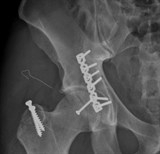

Phẫu thuật thành công cho phi công Canada gãy trật khớp háng nặng

TĐO - Chỉ sau 3 ngày mổ cấp cứu gẫy trật khớp háng nặng do tai nạn giao thông, anh Dustin Spencer (34 tuổi, người Canada) đã có thể bắt đầu tập đi lại. Với một người là phi công thủy phi cơ, sức khỏe là yếu tố sống còn như anh Dustin thì sự hồi phục nhanh chóng phẫu thuật sau ca mổ tại Bệnh viện Đa khoa Quốc tế Vinmec Times City khiến anh rất bất ngờ và hài lòng.

Phẫu thuật thành công cho bệnh nhân bị thoái hóa khớp háng lâu năm

TĐO - Các bác sĩ của Bệnh viện An Bình (TP.HCM) đã thực hiện phẫu thuật thay khớp háng toàn phần thành công cho một bệnh nhân nam bị thoái hóa khớp háng lâu năm, chân trái đã “hụt” mất 2cm.